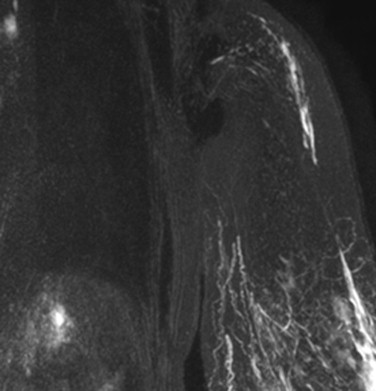

The VGLN flap is suitable for lymphedema stages I–III, even elephantiasis; lymphedema with pain and palsy; lymphedema with chronic infections; lymphedema cases where there is a desire to do the breast at the same time; and lymphedema where there is marked fibrosis in the axilla. Indications of VGLN flap transfer for upper limb lymphedema include total proximal occlusion on lymphoscintigraphy ( Figure 14.3 ) or magnetic resonance lymphangiography ( Figure 14.4 ), failure to complex decongestive treatment and recurrent cellulitis for six months. The contraindications for VGLN flap transfer are local cancer recurrence or distal metastasis. Some patients with brachial plexus neuritis are relative contraindications, but improvements with regional decompression and flap transfer can greatly enhance patients’ quality of life.